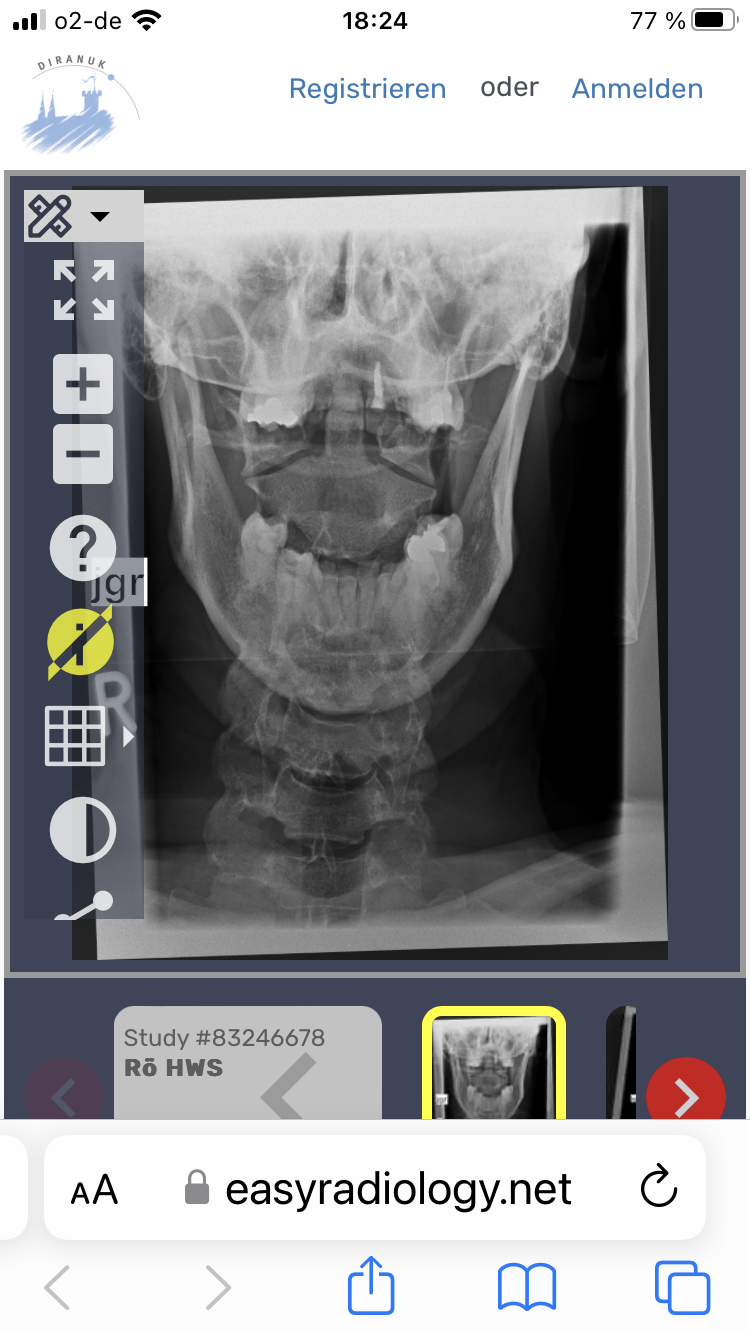

Tinnitus, Schwindel, Kopf- und Nackenschmerzentopic antwortete auf danieks daniek in: Patientenforum Hallo Oli, leider bin ich das Problem weiterhin nicht los geworden und nach wie vor (seid nun knapp 4 Monaten) krank geschrieben. Ich habe nun endlich einen guten Orthopäden gefunden, der mich zum Funktionsröntgen geschickt hat. Auf dem Bild war sichtbar, dass sich der Atlas verschoben und verdreht hat. Der Orthopäde möchte diesen nun beim nächsten Termin korrigieren- ich hoffe einfach das es was bringt und die Odyssee dann ein Ende hat. Zusätzlich bin ich bei einem CMD Spezialisten gewesen und habe eine spezielle Schiene bekommen- bisher merke ich hier aber noch keine Besserung. Konnte bei deiner Freundin schon etwas festgestellt werden? Was mir zumindest etwas geholfen hat ist Ergotherapie und Omega 3 Kapseln.

Hallo zusammen, aufgrund permanenter Nackenschmerzen und weiteren Symptomen wie Schwindel, Tinnitus und Gangunsicherheit wurde bei mir eine Atlasblockade vermutet. Ich habe eine Atlastherapie bei einer speziell dafür ausgebildeten Ergotherapeutin gemacht. Sie meinte der Atlas müsste nun korrekt sitzen. Leider haben sich meine Beschwerden jedoch nicht verbessert und ich ging nochmal zu einem anderen Orthopäden. Dieser vermutet weiterhin eine Atlasblockade und schickte mich zum Funktionsröntgen nach Gutmann/ Biedermann. Die Bilder habe ich einmal angehangen. Leider habe ich den Folgetermin beim Orthopäden erst Mitte Februar und bin nun schon bereits seit Oktober krank geschrieben. Kann man auf den Fotos ggf. eine Atlasblockade erkennen oder bin ich da auf dem völlig falschen Weg? Ich würde gerne endlich wieder arbeiten und zumindest die Schmerzen ein wenig reduzieren können( diverse Schmerzmittel und Muskelentspannungstabletten helfen nicht). Wie wäre anhand der Bilder Eure Einschätzung (mir ist bewusst, das ersetzt natürlich keine ärztliche Untersuchung/ Meinung). schon jetzt vielen Dank! P.S. ein MRT wurde ebenfalls von HWS und BWS gemacht hier wurden zwar Vorwölbungen und Facettengelenksarthrose festgelegt allerdings keine Einengung oder Kompressionen von Nerven etc. Aber diese Schmerzen und der Tinnitus machen mich einfach nur irre!